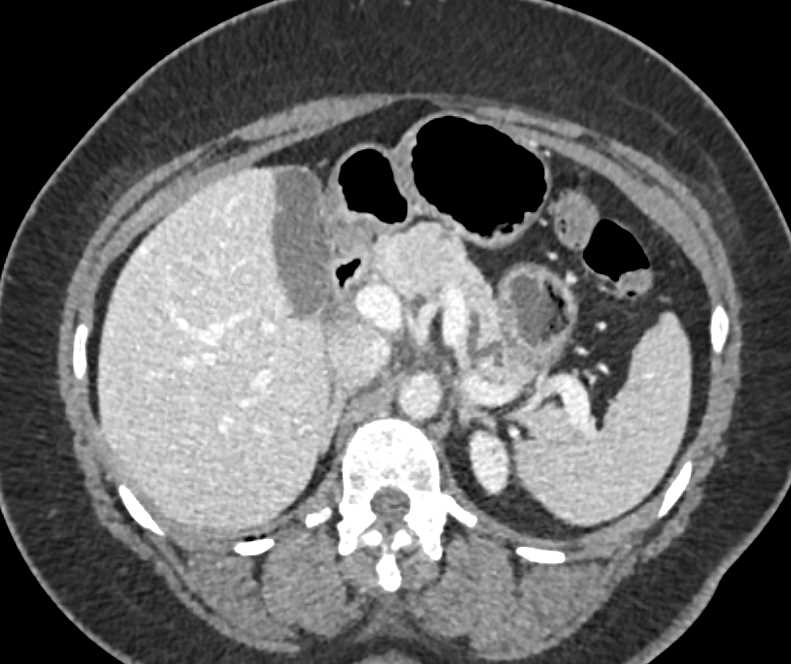

Neuroendocrine Tumor Body of Pancreas